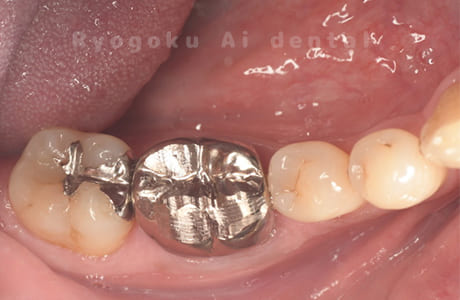

Case06

- しみる症状がある

- 治療内容

- ジルコニアクラウン

- 治療費用

- 165,000円

他院で治療終了となり、しみる症状があると相談された患者さんです。プラスチックの被せ物の隙間が空いてることとプラスチックの被せ物が大きいため、耐久性と審美性を患者さんと相談し、ジルコニアクラウンで治療を行いました。

<リスク・副作用>

過度の咬合や衝撃で割れることがあります。